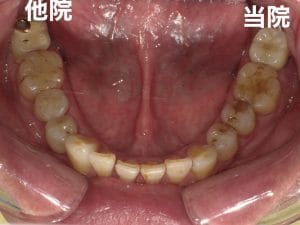

右の奥歯を過去に他院でインプラントをした方が、当院で左下や上の歯のインプラントをする為に転院してくださった患者様です。

インプラントは高額な治療ですが、どこの位置にどの角度で埋入するかが、とても大事というのがわかりやすかったので、患者様に投稿することをお願いして挙げさせていただきました。

インプラントを快適に長く使って頂くには、菌と力のコントロールが大事なのですが、前のものは位置が悪く、汚れも溜まりやすいし、咬む力も変な方向にかかってしまう仕上がりになっています。

被せ物のクオリティーもその歯科医院がどこの技工所にどのブランドで頼むかで全く変わってきます。

インプラントをご検討の方、すでに行った方は参考にしてください。